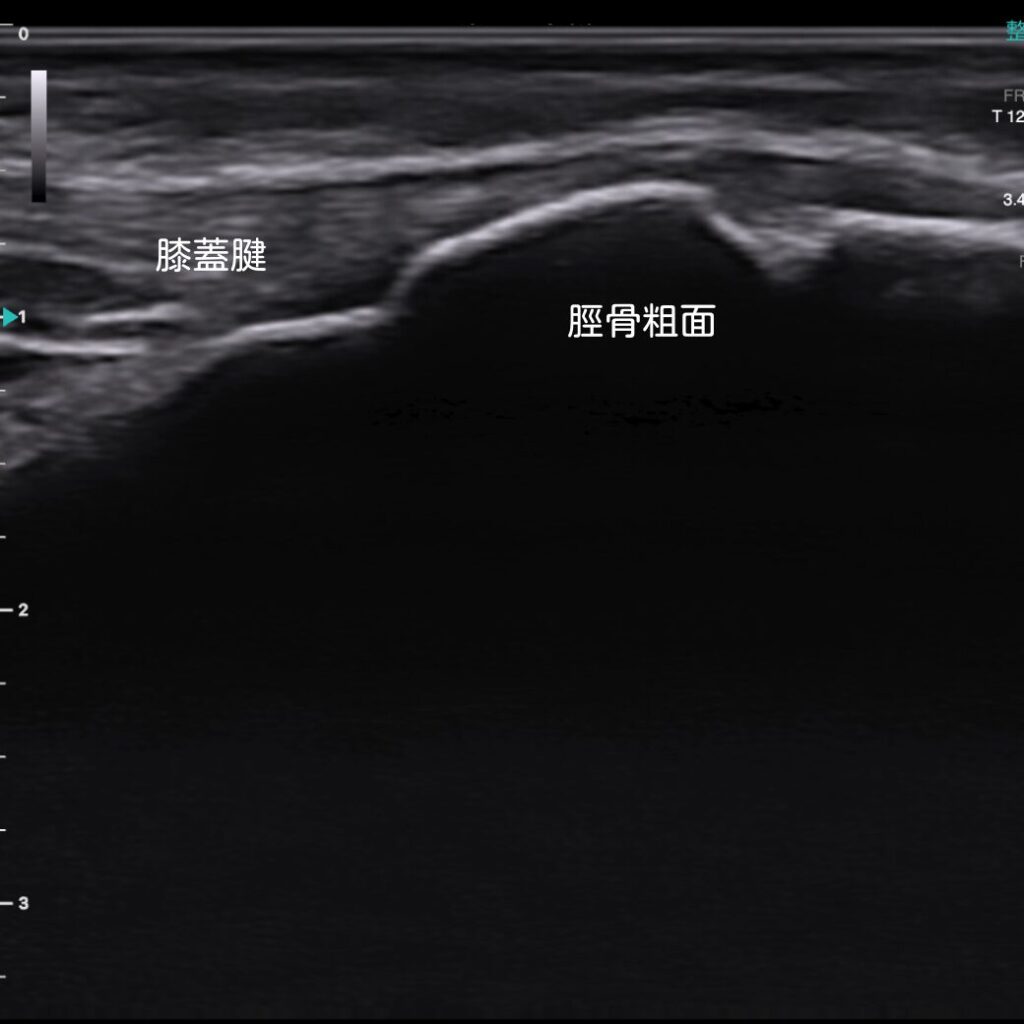

正式名称は「オスグッド・シュラッター病(Osgood-Schlatter Disease)」。膝蓋腱(しつがいけん=膝のお皿とすねをつなぐ腱)が付着する脛骨粗面(けいこつそめん)が繰り返し引っ張られることで、炎症や微細な剥離が生じます。

🔶超音波エコーでリアルタイムに状態を把握

最新の超音波エコーを活用し、痛みの原因や炎症の有無をリアルタイムで可視化。症状の「見える化」により、その時の状態による適切な施術が可能になります。